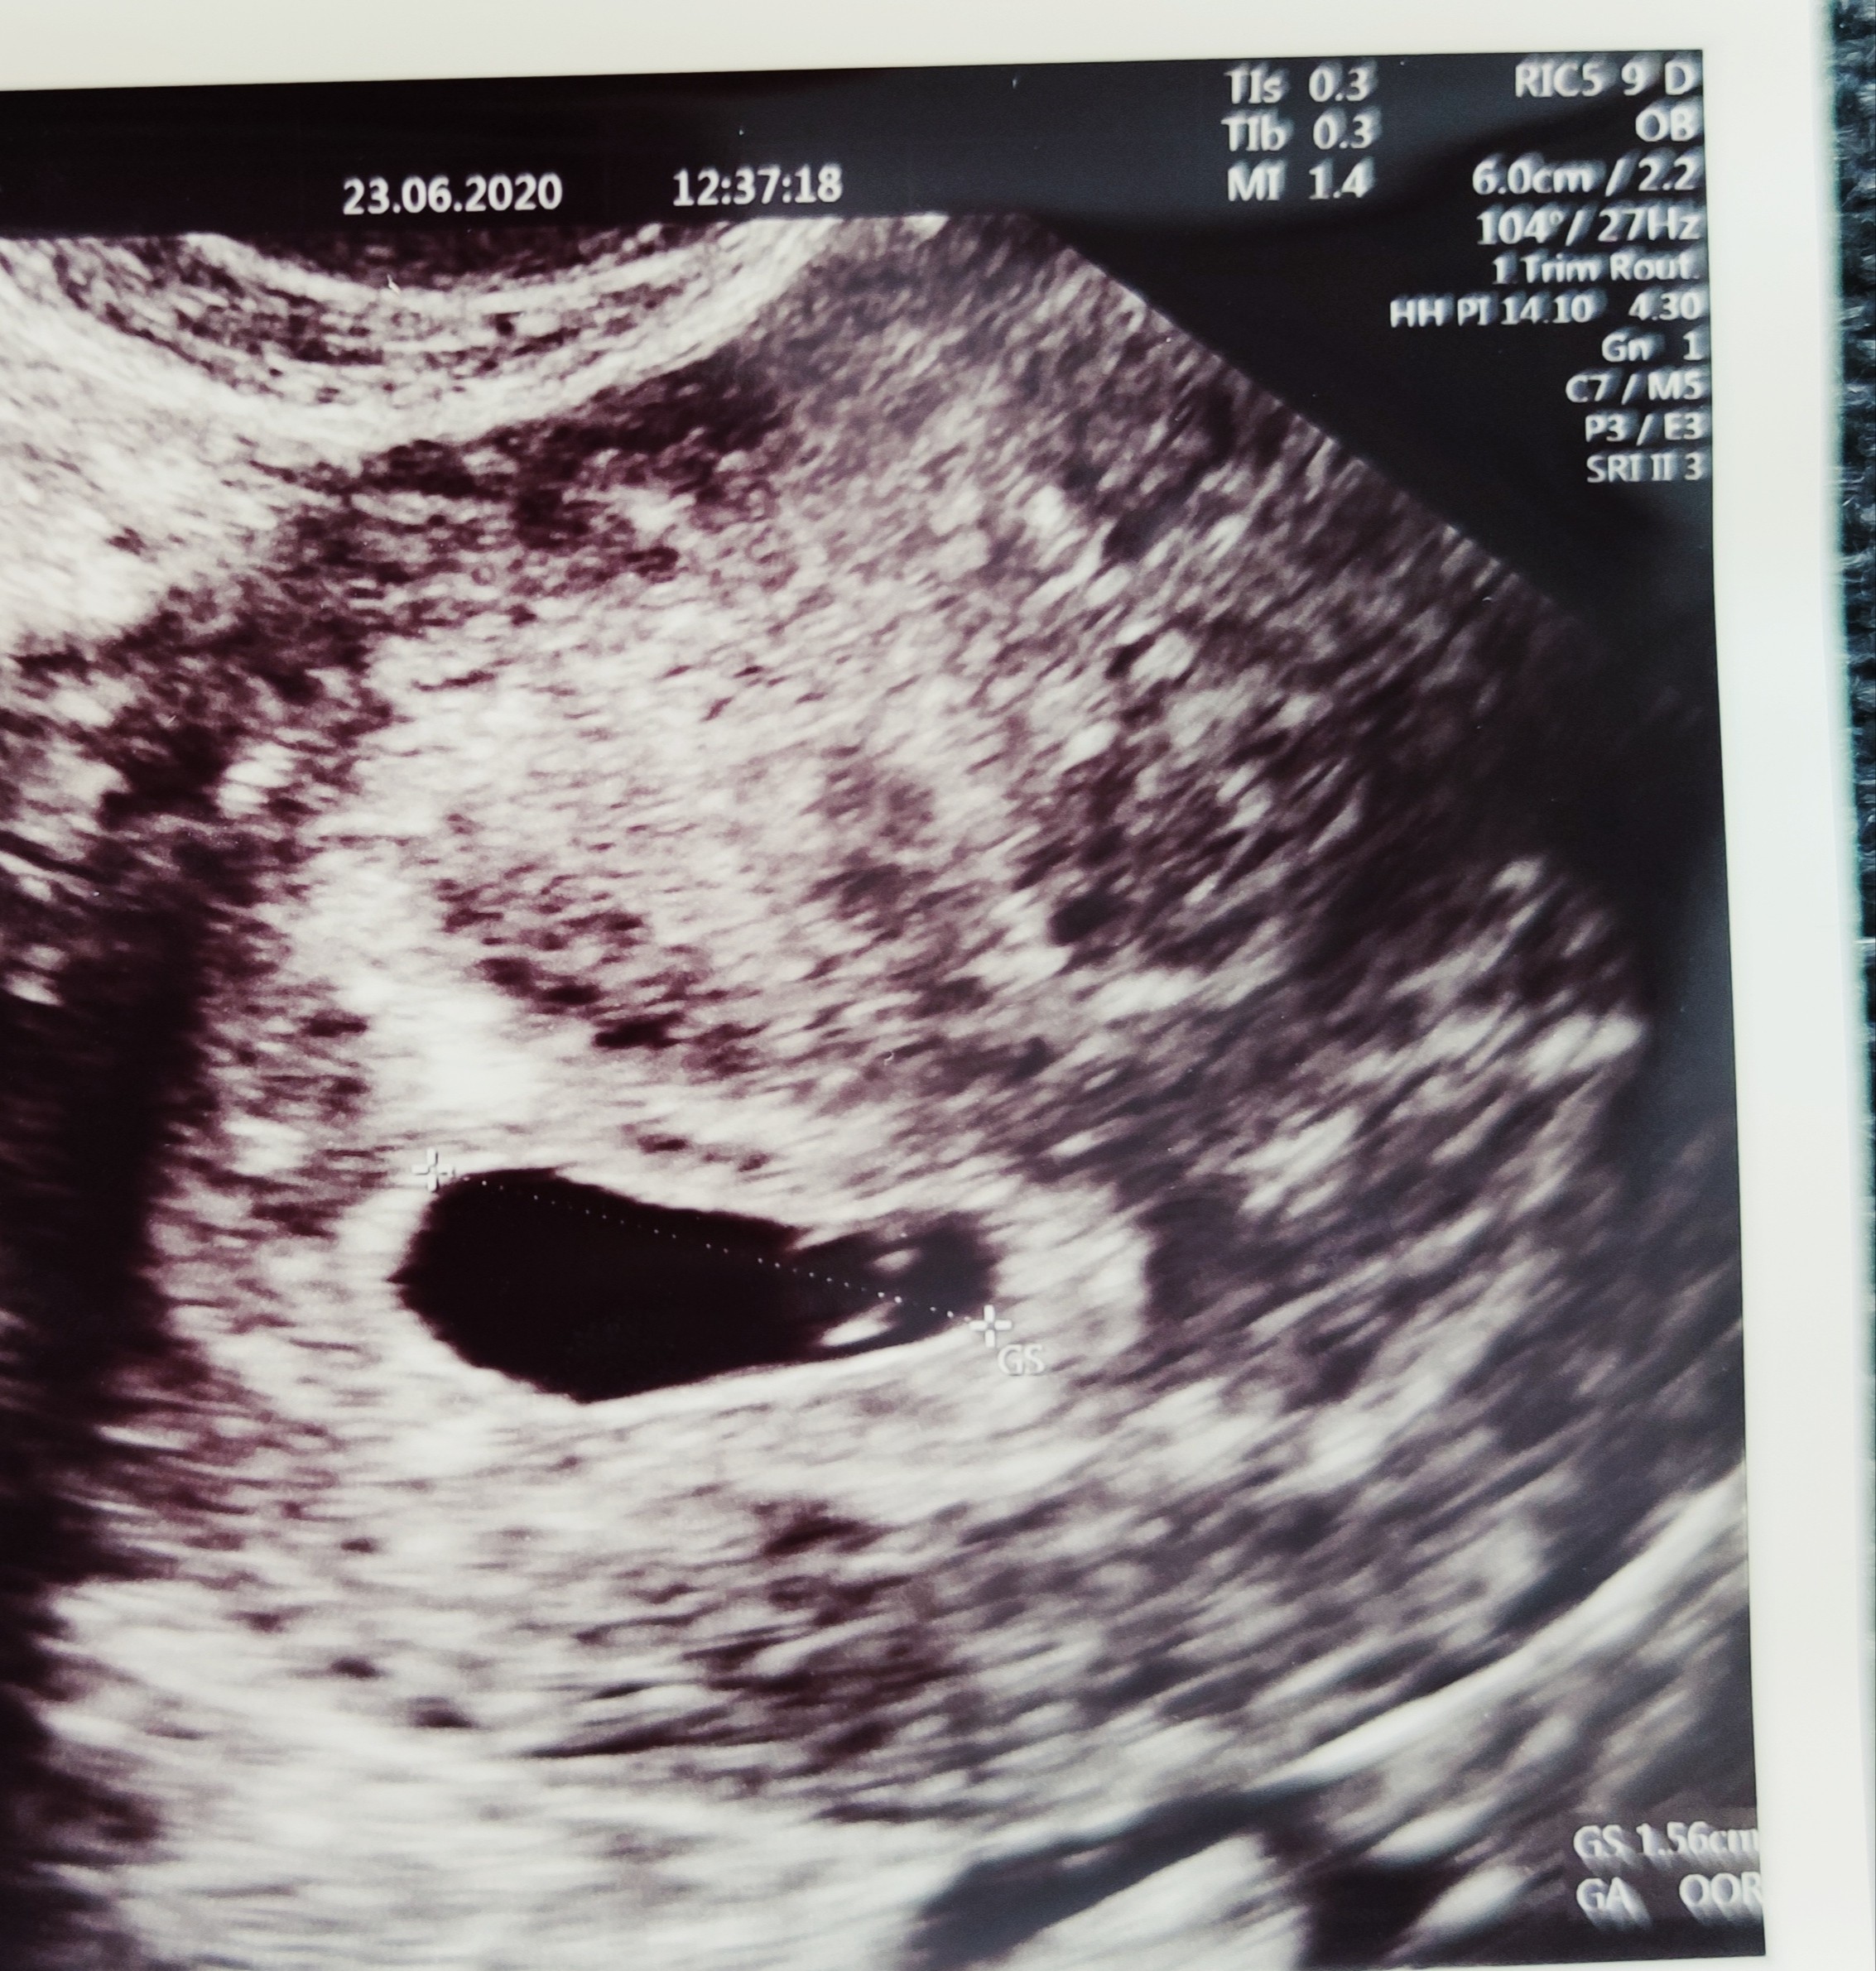

Byłam na pierwszej wizycie 23.06 czyli wg OM 5t+5d wg lekarza pęcherzyk pusty i kolejna wizyta dopiero jutro czyli 7+5

Ostatnio wyciągnęłam to zdjęcie USG a wcześniej na nie nawet nie spojrzałam... I wydaje mi się że zupełnie pusty to on nie jest? Czy to pęcherzyk zoltkowy? Czy jakiś zarys zarodka? Macie jakieś opinie?

Mi to wygląda na żółtkowy i spodziewałabym się za moment zarodka [emoji4] u mnie w 5t5d był tylko ciążowy i żółtkowy a tydzień później widziałam już serduszko [emoji169]